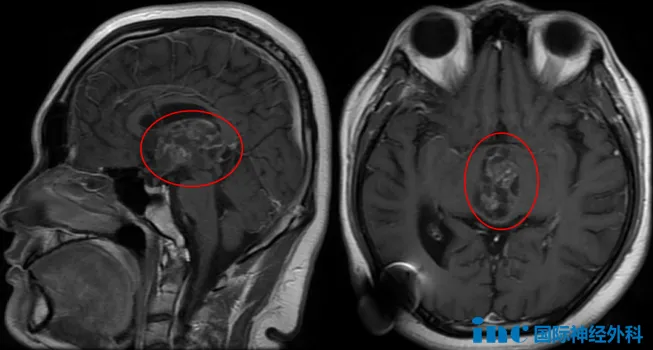

经过5年病程,肿瘤持续生长,患者出现复视、视力下降和视野缺损等新发症状。近期复查MRI显示肿瘤增大至4厘米,占据第三脑室大部分空间。面对病情进展,家长决定寻求巴特朗菲教授的治疗。

肿瘤尺寸达40×25×31毫米,完全占据第三脑室空间,并从室间孔向下压迫中脑结构。手术面临多重技术挑战:手术路径深长狭窄,需切开胼胝体并分离脉络膜裂后在有限操作空间内精确切除肿瘤,对术者操作稳定性要求极高。